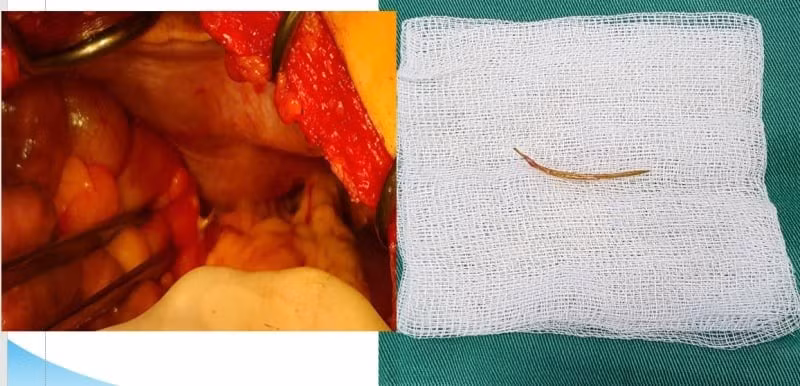

Hình ảnh dị vật xương cá đâm xuyên thành đại tràng bệnh nhân LBS. Ảnh BVCC

Bệnh nhân thứ 2 là bệnh nhân L.B.S (45 tuổi), trú tại phường Bãi Cháy, Hạ Long, Quảng Ninh với triệu chứng đau bụng âm ỉ mạn sườn trái, kèm chướng bụng. Kết quả chụp cắt lớp vi tính cho thấy hình ảnh dị vật xuyên thành đại tràng góc lách, dày thành, thâm nhiễm quanh đại tràng. Bệnh nhân được chẩn đoán: Thủng đại tràng góc lách do dị vật, có chỉ định phẫu thuật lấy dị vật.

Kíp phẫu thuật đã tiến hành bộc lộ đoạn đại tràng góc lách kiểm tra thấy có 1 xương cá từ đại tràng đâm xuyên chồi ra ngoài thành đại tràng khoảng 0,5 cm. Các bác sĩ tiến hành lấy được dị vật dài 3cm, khâu lỗ thủng và lau rửa ổ bụng cho bệnh nhân.